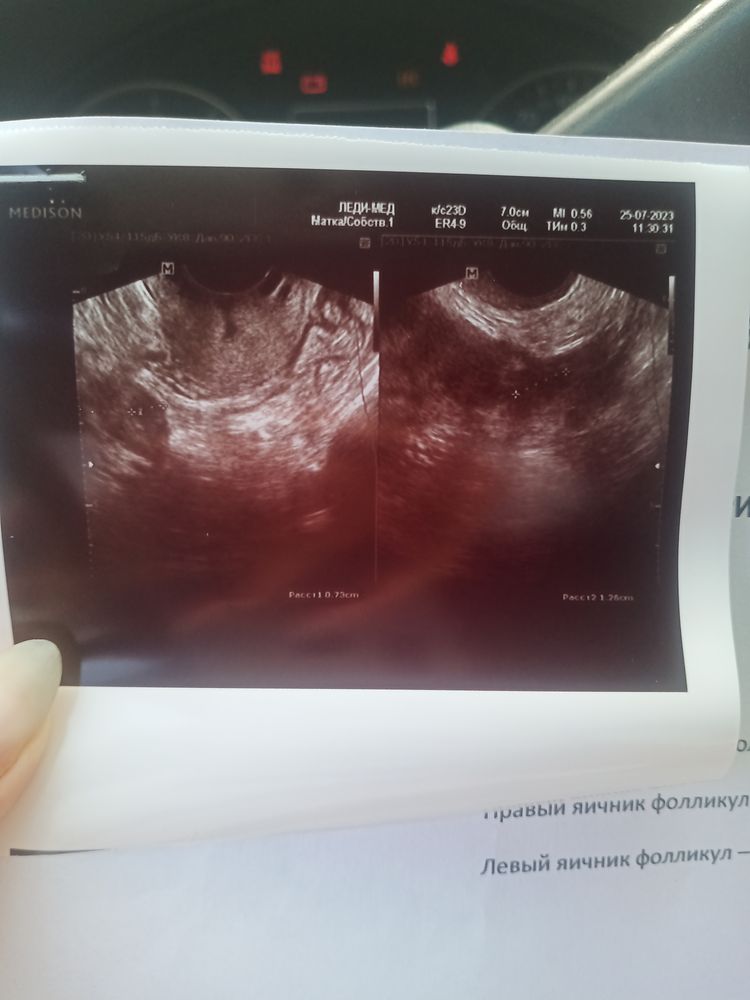

Где на фото узи фолликулы ?

Темные пятна округлой формы с визуально улавливаемыми границами. Они у вас замерены - границы обозначены крестиками, пунктир между ними - диаметр, в правом нижнем углу размер обозначен. Но снимки не очень, плохо видно. Изображение

Ева, спасибо большое. Она мне сказала что они не правильной формы. И типа не ждать о. Что думаете на счет этого ?

А внизу под каждым фото размер их написан

Они у вас там стрелочками выделены даже